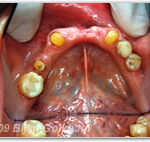

Zähne vor der PZR